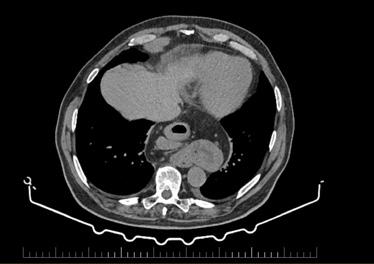

Cazuri disperate în chirurgia cardiacă –atunci când abordul minim invaziv este soluția

Dr. Ion Iovu, Prof. Univ. Dr. Lucian Dorobanțu, Dr. Andreea Bogdan, Dr. Ioana Băjenaru, Dr. Oana Ioniță, Dr. Mădălina Cojocaru, Dr. Toma Iosifescu, Conf. Dr. Cătălin Badiu, Dr. Alexandru Vasilescu